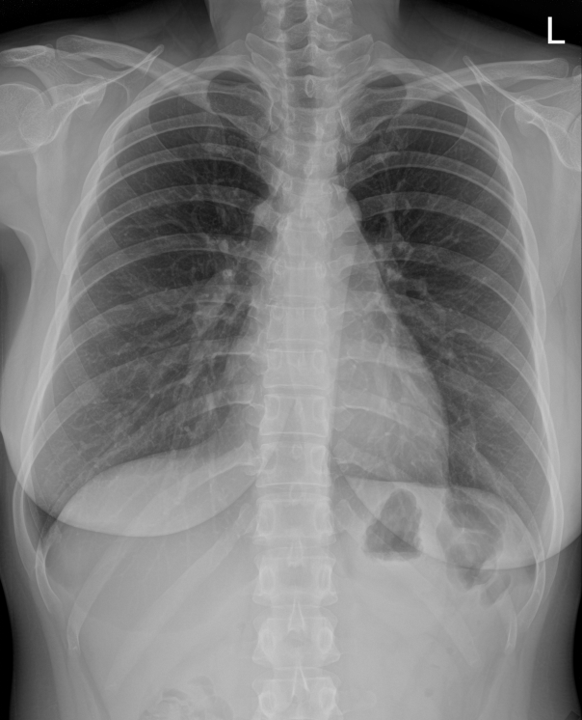

후자의 경우는 사족이 붙어야 한다. 실제로 폐렴이 있어도 엑스레이 상에서 잘 확인이 어려운 경우가 아주 많고, 진행되는 폐렴에서는 아직 영상의학적인 변화가 나타나기 전인 상황이 많아서, 폐렴이 아니라고 확신하는 건 정말 쉽지 않다. 아래 사진을 보자.

이 두 사진은 모두 같은 환자의 다른 날짜에 촬영된 흉부 엑스레이다. 좌우 사진 중 어떤 사진이 더 회복된 상황일까? 우측 사진이다. 잘 보면 우측보다 좌측 음영이 조금 더 blunt 해 보이는 것을 알 수 있다. 사실 이 정도면 의사들 사이에서도 과에 따라서 둘 다 정상, 둘 다 이상, 한쪽만 이상 등으로 갈릴 수 있을 정도의 사진이다.